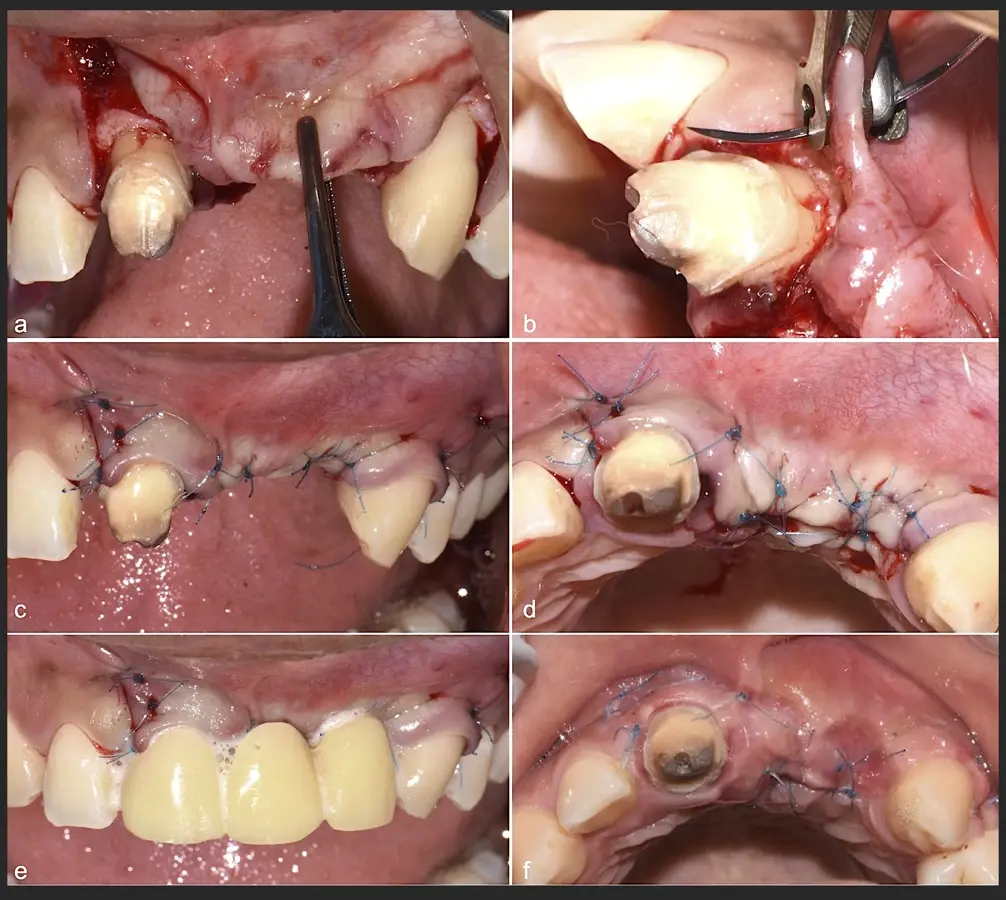

Paciente de sexo femenino de 36 años de edad, llega a la consulta por presentar una restauración protésica inadecuada. En el examen clínico se observa una restauración protésica provisional acrílica sobre las piezas 1.1 y 2.2. Adicionalmente, se aprecia recesión gingival a nivel de la pieza 2.2 y deficiencia horizontal severa de reborde a nivel de la zona edéntula correspondiente a la pieza 2.1. En la evaluación tomográfica se observa ausencia total de tabla ósea vestibular en la pieza 2.2, y se corrobora el déficit en la zona edéntula de la pieza 2.1, para lo cual se indica una reconstrucción de estructuras óseas con hueso en bloque de origen bovino y posteriormente la colocación de implantes dentales.

Figura 43. Colocación del biomaterial triturado (a - d).

Figura 44. Pasos para la colocación de la membrana de barrera (a - d).

Figura 45. Afrontamiento de colgajo y sutura (a - e). Control a los 7 días postquirúrgico (f).